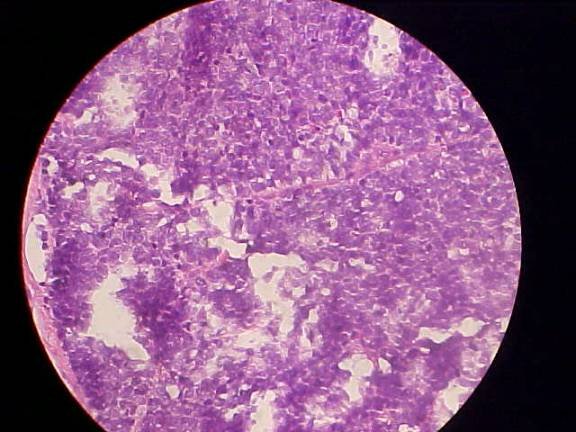

DERMATOHISTOPATHOLOGY:

Poorly differentiated basophilic neoplasm characterized by sheets of atypical basophilic cells, many of which are necrotic and in mitoses. Special stains show that the cells are positive for cytokeratin 20 and neuron-specific enolase. See low low-power and high-power digital photomicrographs below.